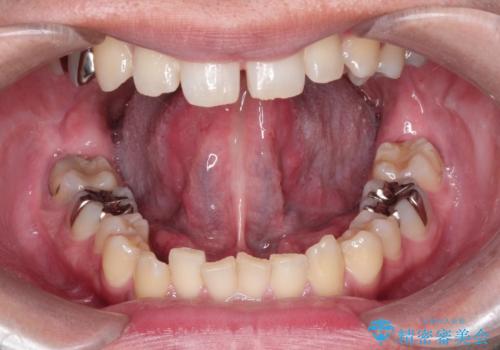

[舌小帯の形成術] 舌の動きが悪い 滑舌を改善したい!

担当医 大元洋佑